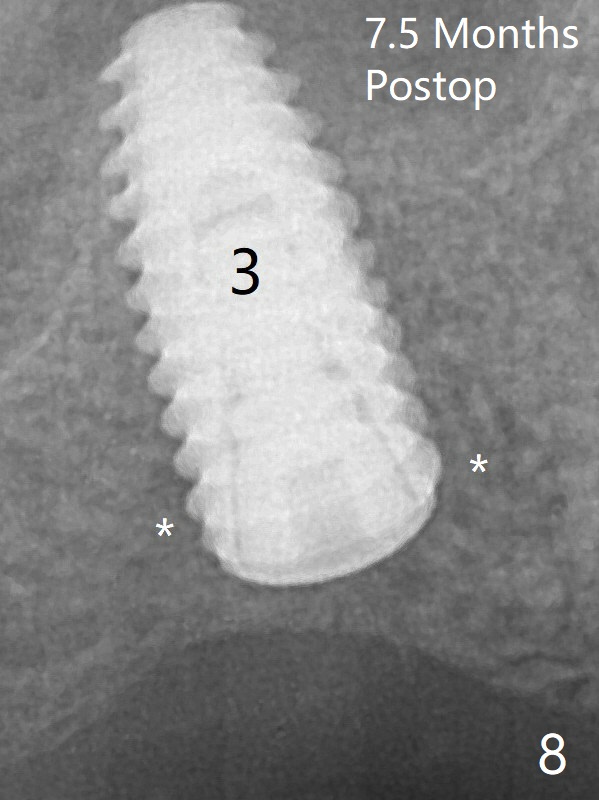

A 4.5x10 mm implant is placed at #3 subcrestal; the healing abutment is incompletely seated (Fig.2). One month postop, the implant is infected with distal bone loss (Fig.4). Bone graft is added. Bone loss seems to reduce 4 months post implant placement (Fig.6 *). Uncover is conducted at the site of #3; there is no superficial infection 7.5 months postop (Fig.8). There is a large buccal defect upon incision with dark hemorrhage. In fact the bone density is low crestally (Fig.8 *). Bone graft is placed for the 2nd time. Eleven months later (1.5 years post implant placement), the bone regrows crestal (Fig.9 *). 保险:愈合螺帽